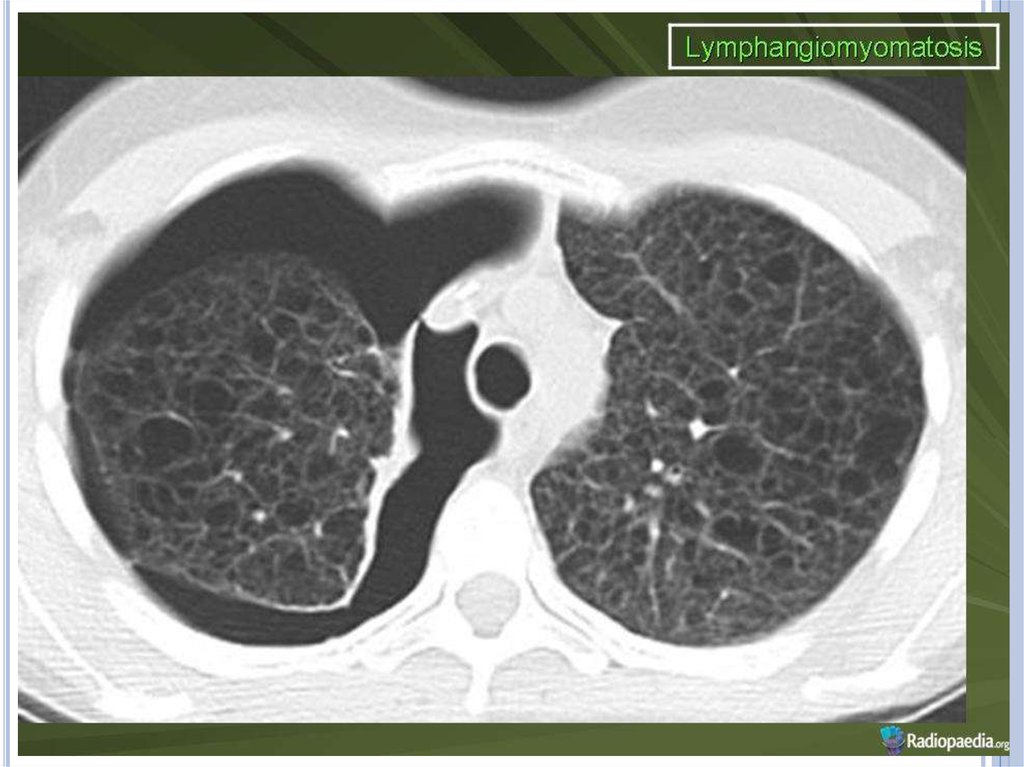

Компьютерная томография легких. Для ЛАМ

характерны множественные диффузные, хорошо очерченные

мелкие тонкостенные кисты. Кисты при этом заболевании

значительно отличаются от зон центрилобулярной эмфиземы

легких, которые не имеют четких границ и своих собственных

стенок, а также от фиброзирующего альвеолита, при котором

основные изменения расположены по периферии легких,

имеются поля фиброза и дезорганизации паренхимы легких,

а кисты расположены субплеврально и

характеризуются довольно толстыми стенками.

Данные компьютерной томографии настолько специфичны

для ЛАМ, что некоторые авторы для постановки точного

диагноза полагают достаточным заключение компьютерной

томографии (КТ) без проведения биопсии легких.